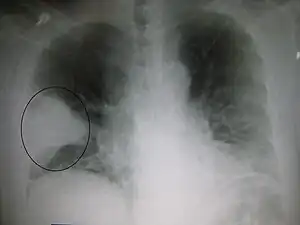

A pneumonia geralmente tem como sua principal rota, a infeção do trato respiratório superior que se desloca para o trato inferior, conhecida como microaspiração..[15] Por outro lado, não é a única rota para alcançar os pulmões; também é possível por via hematogênica (e.g. embolização de endocardite valvar direita), extensão direta e inalação[16][17][18] A causa é geralmente uma infeção com vírus ou bactérias. Entre outras possíveis causas, menos comuns, estão fungos e parasitas, e causas não infecciosas como alguns medicamentos e doenças autoimunes.[4][5] Entre os fatores de risco estão outras doenças pulmonares como a fibrose cística, doença pulmonar obstrutiva crónica e asma, diabetes, insuficiência cardíaca, antecedentes de tabagismo, sistema imunitário debilitado ou comprometimento da capacidade de tossir, como acontece na sequência de um acidente vascular cerebral.[6] O diagnóstico é suspeito com base nos sintomas e num exame físico,[7] podendo ser confirmado por radiografia torácica, análises ao sangue ou cultura microbiológica do muco.[7]